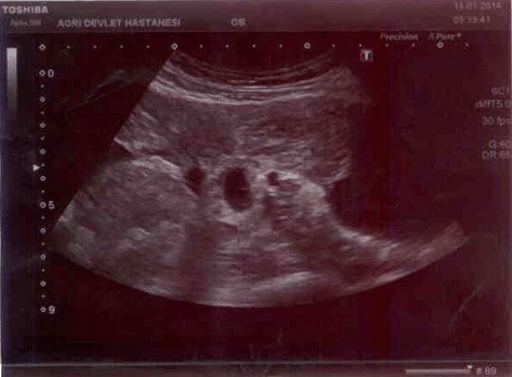

A 21-year-old female admitted into emergency room of Agri Obstetrics and Gynecology Hospital with syncope, nausea, emesis and vaginal hemorrhaging in staining character. She was not having her period for 2 months and was diagnosed with anembryonic pregnancy in another private medical clinic. Eight hours before admission, the patient was treated with dilatation and curettage (D&C) under elective conditions in the same medical clinic she was diagnosed without any complications and the patient was discharged after the operation. Postoperatively 8 hours, the patient gradually started to feel unwell and finally was brought to the emergency room of our hospital. The medical history stated that this was her first pregnancy and she had no history of a coexisting illness or medication. Following admission, no active hemorrhage was diagnosed during speculum inspection but routine hemorrhage in staining character was common following such procedures. Abdominal examination showed a widely distributed tenderness in all quadrants during palpation and rebound finding was prominent in lower quadrants. Dyspnea and palpitations were seen in supine position. Ultrasonography (USG) examination showed a normal uterus, endometrium thickness (10 mm) and normal bilateral ovary structures. Disseminated dense fluid retention in a hemorrhagic fashion was detected in Douglas and paraovarian areas in addition to intestinal segments. The image was consistent with an embryo in yolk sac with a gestational age of 6 weeks and six days in ampullar portion of right fallopian tube. (Figure 1) and (Figure 2). The patient vital signs were blood pressure 80/40 mmHg, pulse 98/minute and hemoglobin was 7.8 g/dl, HTC 22, Platelet count 182000 and WBC 14000. Patient was closely followed and the USG images taken before D&C procedure were obtained from the patient. The images revealed a gestational sac consistent with an anembryonic pregnancy measuring 33 mm located in uterine fundus and the procedure was actually a D&C for abortion (Figure 3) and (Figure 4). Patient's relatives were notified of the medical situation of the patient and our initial diagnoses were either a uterine rupture or a coexisting pregnancy of a heterotopic type. Laparotomy was planned after assessment of the clinical situation of the patient and risks and details of the procedure was shared with the patient. After obtaining 3 units of erythrocyte suspension, the abdominal access was done using a Pfannenstiel incision. Dense disseminated fluid was detected and about 2 liters. of this hemorrhagic fluid was aspirated. After aspiration, no signs of perforation was found on the front or rear surface of the uterus. In tubal structures inspection, left tube and ovary was normal but right tube had an actively bleeding gestational sac about 2 cm in diameter on ampullary portion and a full thickness perforated tubular structure confirmed our diagnosis of heterotopic pregnancy (Figure 5). Salpingostomy was chosen after considering patient's age and gravidity. The tube was repaired using 3–0 Prolene sutures after removal of all trophoblastic structures. Operation was finished after checking for hemorrhage and an abdominal drainage tube was inserted for follow-up. Three units erythrocyte suspension was used during the operation. Within 48 hours in postoperative period, 50 cm3 serohemorrhagic fluid was collected in the drain. The abdominal drainage tube was removed on the third day of operation and patient was discharged from the hospital with full recovery. The patient was advised to go to regular follow-up in gynecology and obstetrics clinic. b-hCG values dropped below 5 and no complications were seen in incisional scar area. She was also informed about the possible risks that might occur in future pregnancies.

Figure 2: Expansive fluid seen in abdomen of the case admitted with acute abdominal findings.